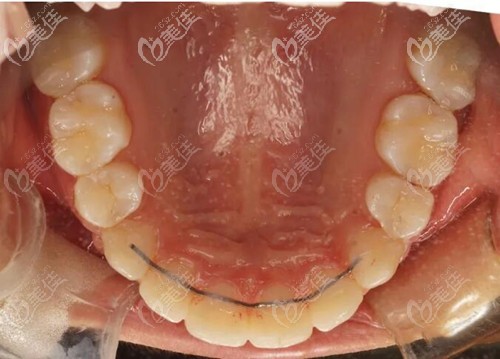

鄭州金水春芽口腔門診部

人氣 0.2 活躍 6.8 診療科目 口腔科 //醫(yī)學影像科 | X線診斷專業(yè)(限口腔)******